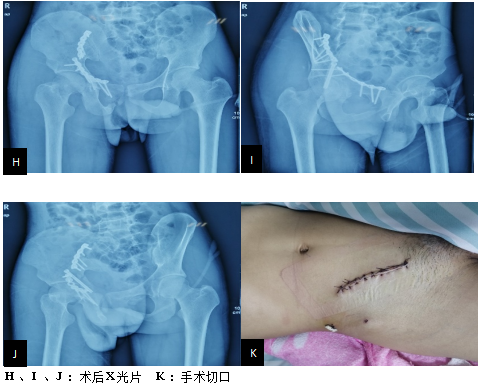

以下图片是我科骨盆髋臼骨折腹直肌外侧入路手术技术的两例患者资料。(骨二科)

实例一

实例二